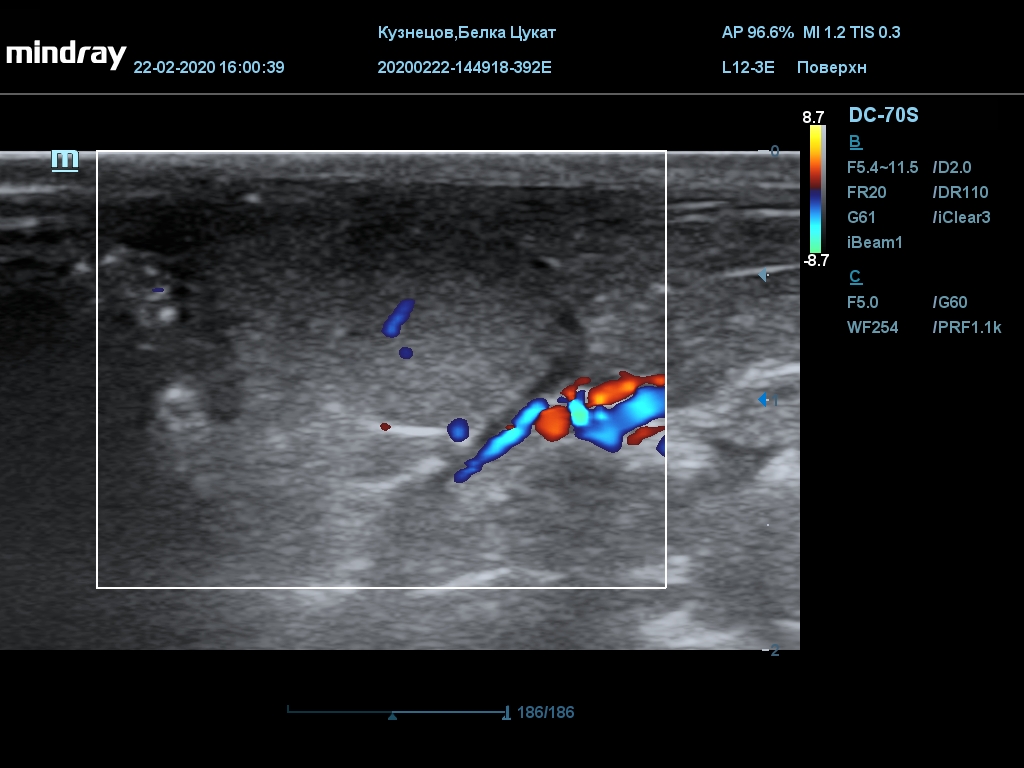

УЗИ

(почки, мочевой пузырь и, предположительно, простата)

Обращаю внимание, что делала УЗИ и писала заключение узист, которая специализируется на кошках и собаках, поэтому она сделала узи и описала, как смогла, но тонкостей грызунячьей анатомии она не знает.

Приложил только фото, есть ещё пара видео, но не знаю, как тут выложить, и надо ли.

Каудальнее мочевого пузыря визуализируется округлая структура размером 11,1 х 8,3 мм с ровными контурами гипоэхогенная однородная, с признаками васкуляризации.

Заключение: УЗпризнаки уролитиаза, объёмная структура каудальнее мочевого пузыря. Признаки расширения левой лоханки.

УЗИ

(почки, мочевой пузырь и, предположительно, простата)

Обращаю внимание, что делала УЗИ и писала заключение узист, которая специализируется на кошках и собаках, поэтому она сделала узи и описала, как смогла, но тонкостей грызунячьей анатомии она не знает.

Каудальнее мочевого пузыря визуализируется округлая структура размером 11,1 х 8,3 мм с ровными контурами гипоэхогенная однородная, с признаками васкуляризации.

Заключение: УЗпризнаки уролитиаза, объёмная структура каудальнее мочевого пузыря. Признаки расширения левой лоханки.